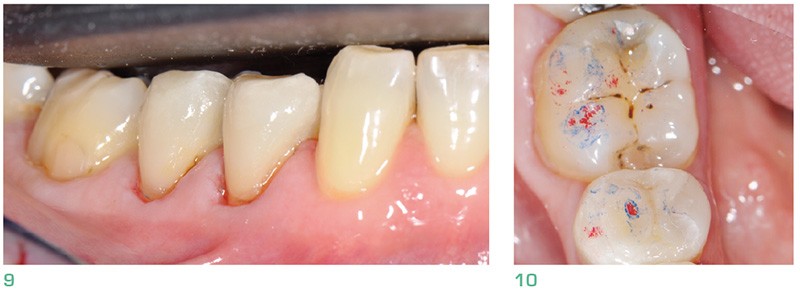

Dans le cas d’usure située en vestibulaire et en occlusal : consommation de boissons acides ou abrasion occlusale liée à de l’abfraction cervicale par exemple, sont des cas typiques d’usure, rencontrés notamment au niveau des prémolaires [4].

Outre les lésions d’usure, les veneerlays présentent également un intérêt esthétique sur des dents postérieures nécessitant des restaurations occlusales…